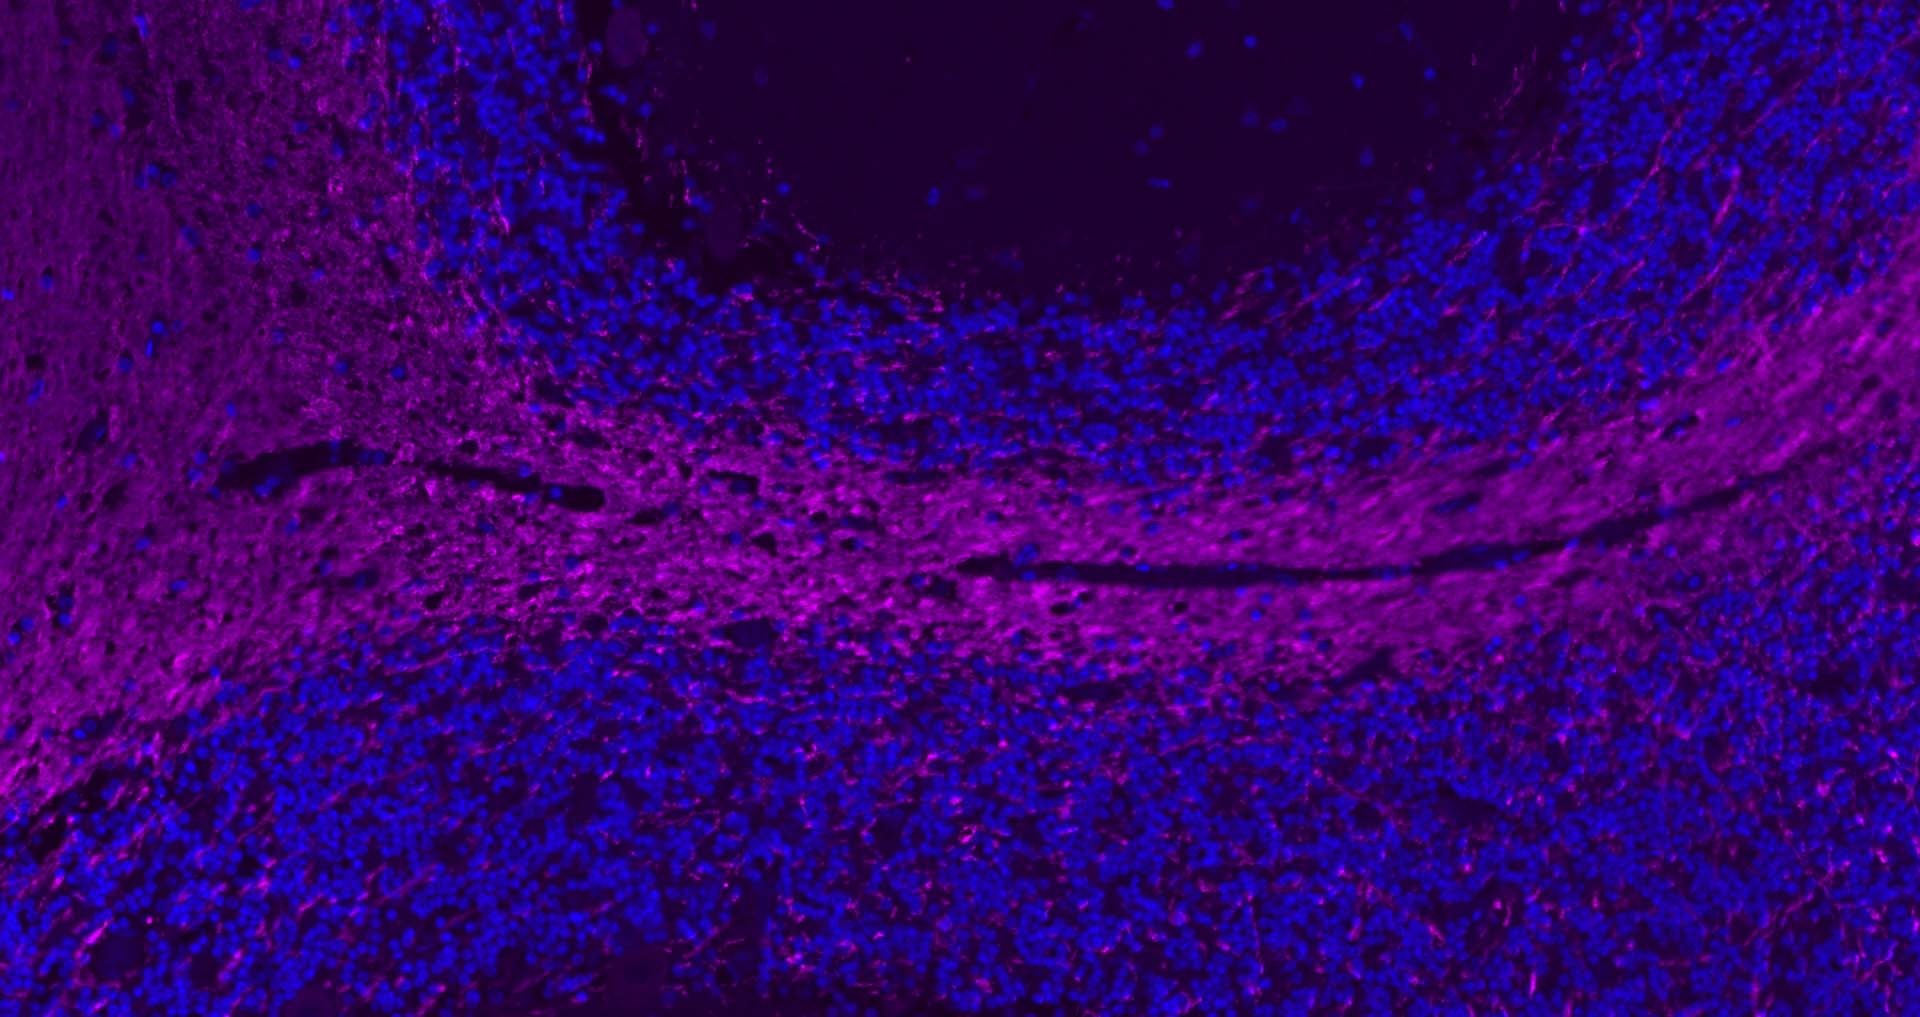

| Verified Activity | 1. 25 μg total protein per Lane of various lysates probed with MBP polyclonal antibody, unconjugated (TMAB-01109) at 1:1000 dilution and 4°C overnight incubation. Followed by conjugated secondary antibody incubation at RT for 60 min. 2. Paraformaldehyde-fixed, paraffin embedded Mouse Cerebrum; Antigen retrieval by boiling in sodium citrate buffer (pH6.0) for 15 min; Antibody incubation with MBP Polyclonal Antibody, Unconjugated (TMAB-01109) at 1:200 overnight at 4°C, followed by conjugation to the SP Kit (Rabbit) and DAB staining. 3. Paraformaldehyde-fixed, paraffin embedded Mouse Cerebellum; Antigen retrieval by boiling in sodium citrate buffer (pH6.0) for 15 min; Antibody incubation with MBP Polyclonal Antibody, Unconjugated (TMAB-01109) at 1:200 overnight at 4°C, followed by conjugation to the SP Kit (Rabbit) and DAB staining. 4. Paraformaldehyde-fixed, paraffin embedded Rat Cerebellum; Antigen retrieval by boiling in sodium citrate buffer (pH6.0) for 15 min; Antibody incubation with MBP Polyclonal Antibody, Unconjugated (TMAB-01109) at 1:200 overnight at 4°C, followed by conjugation to the SP Kit (Rabbit) and DAB staining. 5. Paraformaldehyde-fixed, paraffin embedded Rat Cerebrum; Antigen retrieval by boiling in sodium citrate buffer (pH6.0) for 15 min; Antibody incubation with MBP Polyclonal Antibody, Unconjugated (TMAB-01109) at 1:200 overnight at 4°C, followed by conjugation to the SP Kit (Rabbit) and DAB staining. 6. Paraformaldehyde-fixed, paraffin embedded Human Cerebrum; Antigen retrieval by boiling in sodium citrate buffer (pH6.0) for 15 min; Antibody incubation with MBP Polyclonal Antibody, Unconjugated (TMAB-01109) at 1:200 overnight at 4°C, followed by conjugation to the SP Kit (Rabbit) and DAB staining. 7. Paraformaldehyde-fixed, paraffin embedded Rat Cerebrum; Antigen retrieval by boiling in sodium citrate buffer (pH6.0) for 15 min; Antibody incubation with MBP Polyclonal Antibody, Unconjugated (TMAB-01109) at 1:200 overnight at 4°C. Followed by conjugated Goat Anti-Rabbit IgG antibody (green), DAPI (blue) was used to stain the cell nucleus. 8. Paraformaldehyde-fixed, paraffin embedded Human Cerebrum; Antigen retrieval by boiling in sodium citrate buffer (pH6.0) for 15 min; Antibody incubation with MBP Polyclonal Antibody, Unconjugated (TMAB-01109) at 1:200 overnight at 4°C. Followed by conjugated Goat Anti-Rabbit IgG antibody (green), DAPI (blue) was used to stain the cell nucleus. 9. Paraformaldehyde-fixed, paraffin embedded Mouse Cerebrum; Antigen retrieval by boiling in sodium citrate buffer (pH6.0) for 15 min; Antibody incubation with MBP Polyclonal Antibody, Unconjugated (TMAB-01109) at 1:200 overnight at 4°C. Followed by conjugated Goat Anti-Rabbit IgG antibody (Rose red), DAPI (blue) was used to stain the cell nucleus. 10. Paraformaldehyde-fixed, paraffin embedded Mouse Cerebellum; Antigen retrieval by boiling in sodium citrate buffer (pH6.0) for 15 min; Antibody incubation with MBP Polyclonal Antibody, Unconjugated (TMAB-01109) at 1:200 overnight at 4°C. Followed by conjugated Goat Anti-Rabbit IgG antibody (Rose red), DAPI (blue) was used to stain the cell nucleus. 11. Paraformaldehyde-fixed, paraffin embedded Rat Cerebellum; Antigen retrieval by boiling in sodium citrate buffer (pH6.0) for 15 min; Antibody incubation with MBP Polyclonal Antibody, Unconjugated (TMAB-01109) at 1:200 overnight at 4°C. Followed by conjugated Goat Anti-Rabbit IgG antibody (Rose red), DAPI (blue) was used to stain the cell nucleus. 12. Paraformaldehyde-fixed, paraffin embedded Human Cerebellum; Antigen retrieval by boiling in sodium citrate buffer (pH6.0) for 15 min; Antibody incubation with MBP Polyclonal Antibody, Unconjugated (TMAB-01109) at 1:200 overnight at 4°C. Followed by conjugated Goat Anti-Rabbit IgG antibody (Rose red), DAPI (blue) was used to stain the cell nucleus. 13. Paraformaldehyde-fixed, paraffin embedded Human Left Parietal Lobe; Antigen retrieval by boiling in sodium citrate buffer (pH6.0) for 15 min; Antibody incubation with MBP Polyclonal Antibody, Unconjugated (TMAB-01109) at 1:200 overnight at 4°C. Followed by conjugated Goat Anti-Rabbit IgG antibody (Rose red), DAPI (blue) was used to stain the cell nucleus. ![]() ![]() ![]() ![]() ![]() ![]() ![]() ![]() ![]() ![]() ![]() ![]() ![]() |